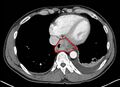

![]() | |

| Endoscopic image of an esophageal adenocarcinoma | |

Although an occlusive tumor may be suspected on a barium swallow or barium meal, the diagnosis is best made with an examination using an endoscope. This involves the passing of a flexible tube with a light and camera down the esophagus and examining the wall, and is called an esophagogastroduodenoscopy. Biopsies taken of suspicious lesions are then examined histologically for signs of malignancy.